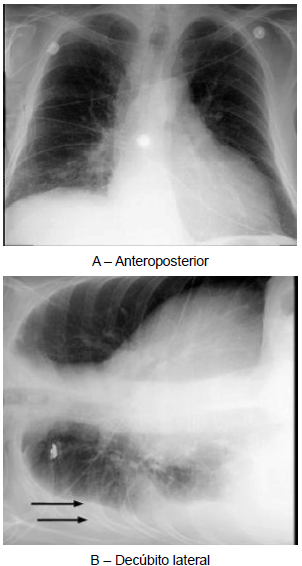

As radiografias acima foram realizadas em paciente com história de trauma torácico, cujo diagnóstico clínico-radiológico é